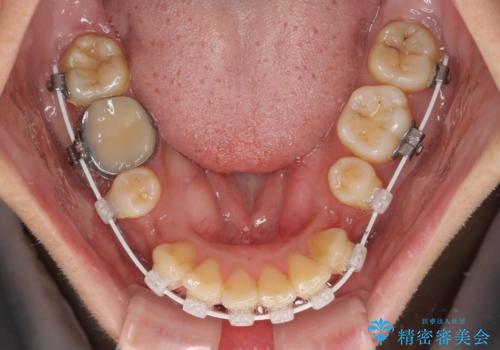

- 審美装置

- 1年7ヶ月

- 10-30回

上下前歯がくちばしのように突出していたため、上下左右の第一小臼歯4本を抜歯し、ワイヤー装置にて矯正治療を行うこととしました。